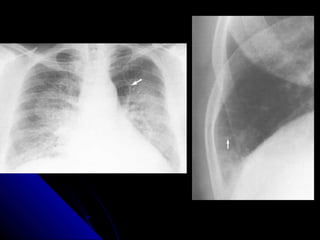

NNoodduullee//mmaassss

NNoodduulleess aanndd mmaasssseess iinn tthhee lluunngg aappppeeaarr aass

rroouunndd wwhhiittee lleessiioonnss.. IIff tthhee lleessiioonn mmeeaassuurreess lleessss

tthhaann 33 ccmm,, iitt iiss ccaalllleedd aa nnoodduullee.. IIff iitt iiss llaarrggeerr tthhaann

33 ccmm,, iitt iiss ccaalllleedd aa mmaassss..

AA nnoodduullee//mmaassss iiss ccaauusseedd bbyy eeiitthheerr aa mmaalliiggnnaanntt

((ee..gg.. lluunngg ccaanncceerr,, mmeettaassttaassiiss)) oorr bbeenniiggnn pprroocceessss

((ee..gg.. hhaammaarrttoommaa,, ggrraannuulloommaa))..

PPrriimmaarryy lluunngg ccaanncceerrss tteenndd ttoo hhaavvee iillll--ddeeffiinneedd,,

ssppiiccuullaatteedd bboorrddeerrss.. MMeettaassttaasseess tteenndd ttoo pprroodduuccee

mmuullttiippllee ssmmooootthh rroouunndd lluunngg nnoodduulleess,, oofftteenn ooff

vvaarriiaabbllee ssiizzee.. BBeenniiggnn lleessiioonnss tteenndd ttoo bbee ssmmaallll,,

wweellll ddeeffiinneedd,, ssmmooootthh,, rroouunndd aanndd mmaayybbee ccaallcciiffiieedd..